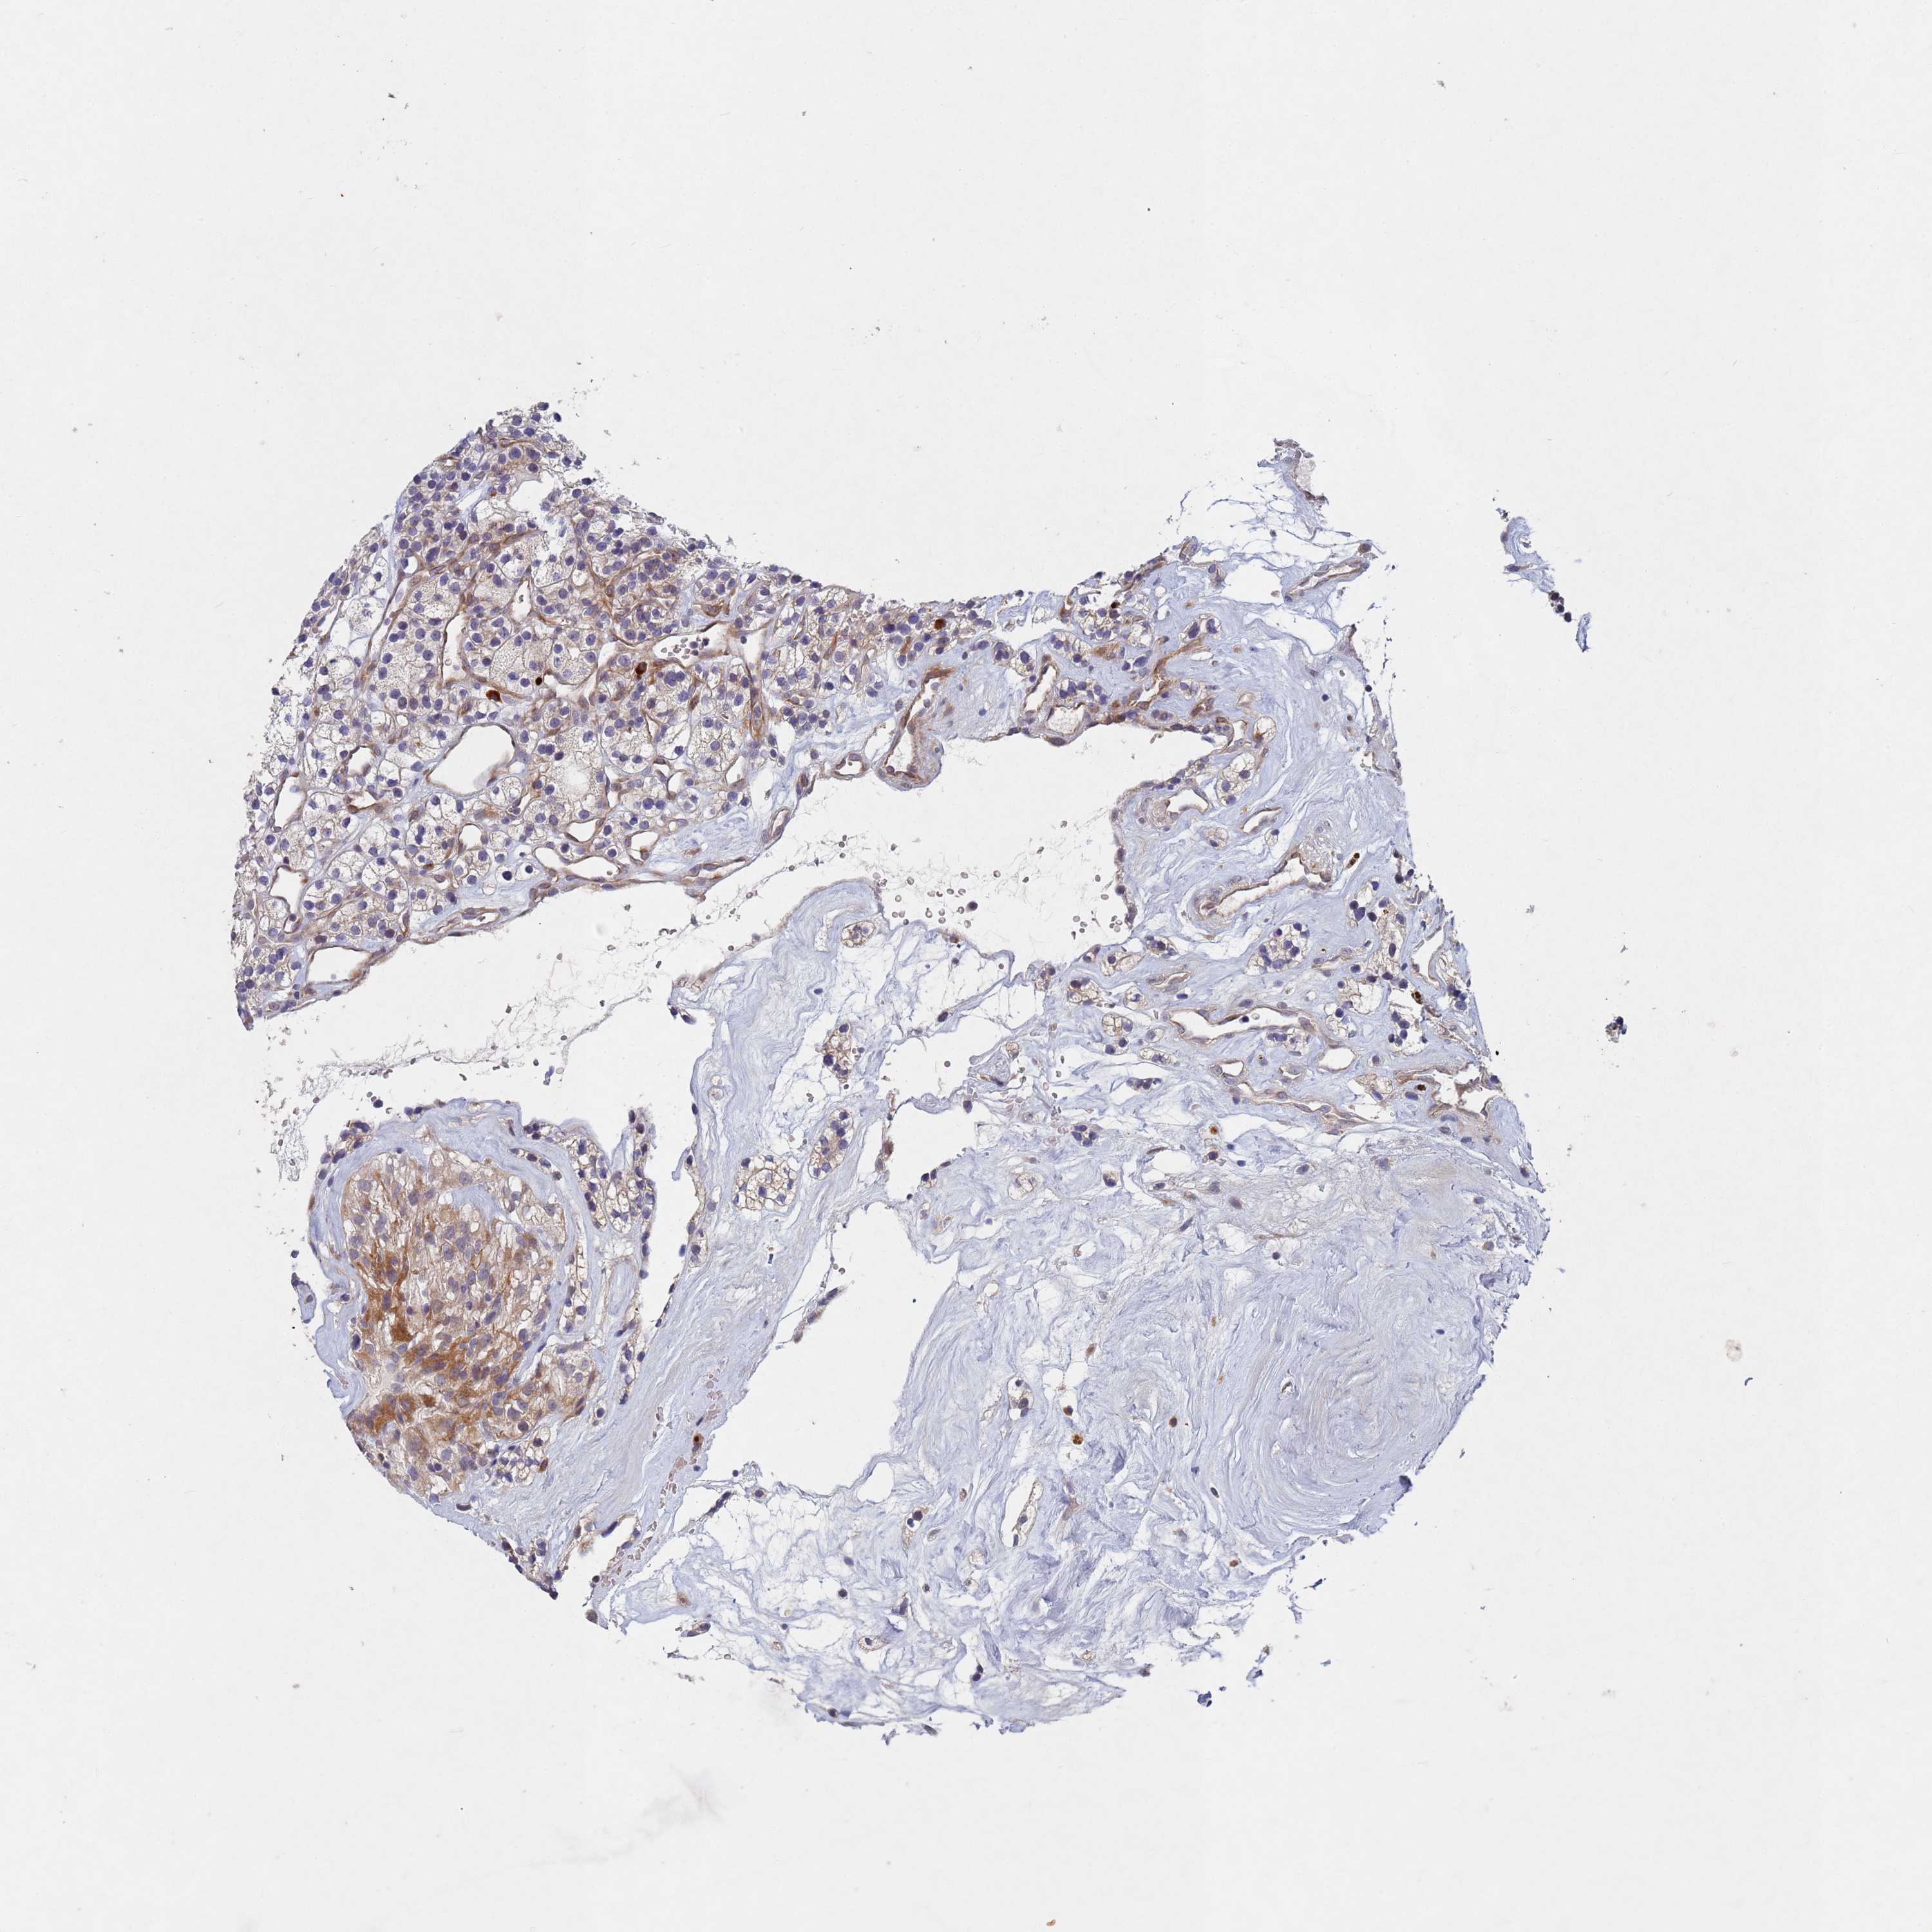

KIDNEY RENAL CLEAR CELL CARCINOMA (VALIDATION) - Interactive survival scatter ploti

The Survival Scatter plot shows the clinical status (i.e. dead or alive) for all individuals in the patient cohort, based on the same data that underlies the corresponding Kaplan-Meier plots. Patients that are alive at last time for follow-up are shown in blue and patients who have died during the study are shown in red.

The x-axis shows the expression levels (FPKM) of the investigated gene in the tumor tissue at the time of diagnosis. The y-axis shows the follow-up time after diagnosis (years). Both axes are complimented with kernel density curves demonstrating the data density over the axes. The top density plot shows the expression levels (FPKM) distribution among dead (red) and alive patients (blue). The right density plot shows the data density of the survived years of dead patients with high and low expression levels respectively, stratified using the cutoff indicated by the vertical dashed line through the Survival Scatter plot. This cutoff is automatically defined based on the FPKM cutoff that minimizes the p-score. The cutoff can be changed by dragging the vertical line or by entering a cutoff value in the square labeled "Current cut-off".

Under the Survival Scatter plot the p-score landscape (black curve; left axis) is shown together with dead median separation (red curve; right axis). Dead median separation is the difference in median mRNA expression between patients who have died with high and low expression, respectively. It is calculated as follows: median FPKM expression of dead patients with high expression - median FPKM expression of dead patients with low expression. This is intended to aid the user in visually exploring custom cutoffs and the associated p-scores and dead median separation.

Individual patient data is displayed and can be filtered by clicking on one or more of the category buttons on the top of the page. Categories describing expression level and patient information include: high, low, alive, dead, female, male and tumor stages. The scale of the x-axis can be toggled between linear and log-scale by clicking on the "x log" button. Mouse-over function shows TCGA ID, patient information and mRNA expression (FPKM) for each patient.

& Survival analysisi

Kaplan-Meier plots summarize results from analysis of correlation between mRNA expression level and patient survival. Patients were divided based on level of expression into one of the two groups "low" (under cut off) or "high" (over cut off). X-axis shows time for survival (years) and y-axis shows the probability of survival, where 1.0 corresponds to 100 percent.

TNPO2 is not prognostic in Kidney Renal Clear Cell Carcinoma (validation)

Best expression cut offi

Based on the FPKM value of each gene, patients were classified into two groups and association between prognosis (survival) and gene expression (FPKM) was examined. The best expression cut-off refers the FPKM value that yields maximal difference with regard to survival between the two groups at the lowest log-rank P-value. Best expression cut-off was selected based on survival analysis .

When clicking on this number, the vertical dashed line indicating cut-off, the interactive survival plot, and the Kaplan-Meier curve will be adjusted to show results based on the best expression cut-off.

: 28.59

Median expressioni

Median expression refers to the median FPKM value calculated based on the gene expression (FPKM) data from all patients in this dataset. When clicking on this number, the vertical dashed line indicating cut-off, the interactive survival plot, and the Kaplan-Meier curve will be adjusted to show results based on the median expression.

: N/A

Median follow up timei

Median follow up time refers to the median time (years) after diagnosis with this type of cancer, based on clinical data from all patients in this dataset.

P scorei

Log-rank P value for Kaplan-Meier plot showing results from analysis of correlation between mRNA expression level and patient survival.

N/A

5-year survival highi

5-year survival for patients with higher expression than the expression cutoff.

For melanoma and glioma, 3-year survival is shown.

5-year survival lowi

5-year survival for patients with lower expression than the expression cutoff.

TCGA RNA samplesi

RNA-seq data is reported as average FPKM (number Fragments Per Kilobase of exon per Million reads), generated by the The Cancer Genome Atlas (TCGA) .

Normal distribution across the dataset is visualized with box plots, shown as median and 25th and 75th percentiles. Points are displayed as outliers if they are above or below 1.5 times the interquartile range. FPKM values of the individual samples are presented next to the box plot.

Average pTPM 30.6

Number of samples 100